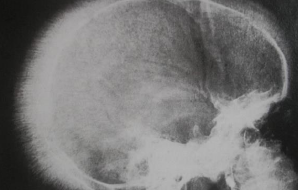

- Sunrise skull bone (Hair-on-end)

- 造血細胞/ 骨增生

- 長骨骨隨增生

- 扁平骨變寬